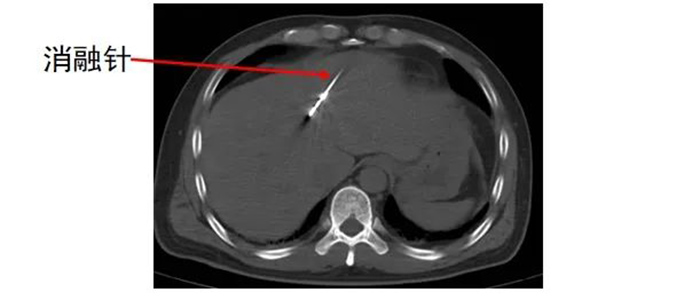

经多学科讨论,齐先生适合转化治疗,首先利用消融的方法解决肝内转移瘤,同时根据病理科基因检测结果进行全身系统治疗,待转化治疗成功,肿瘤缩小、降期后,吻合口复发区域再进行手术切除。 肿瘤科、麻醉手术科 及放射影像科协同合作 为齐先生进行 经皮肝恶性肿瘤微波消融术

齐先生病灶临近大血管、重要脏器。91club 专家团队在CT引导下精准定位,经皮穿刺将微波消融针准确置入齐先生肝脏肿瘤部位,然后利用微波能量,使肿瘤组织内的水分子快速振动、摩擦产生热量,从而使局部温度迅速升高,让肿瘤细胞凝固性坏死。整个手术过程顺利,避免了严重并发症发生。

准确插入到病灶内,并避开了门静脉左支及分支,避免了出血并发症。